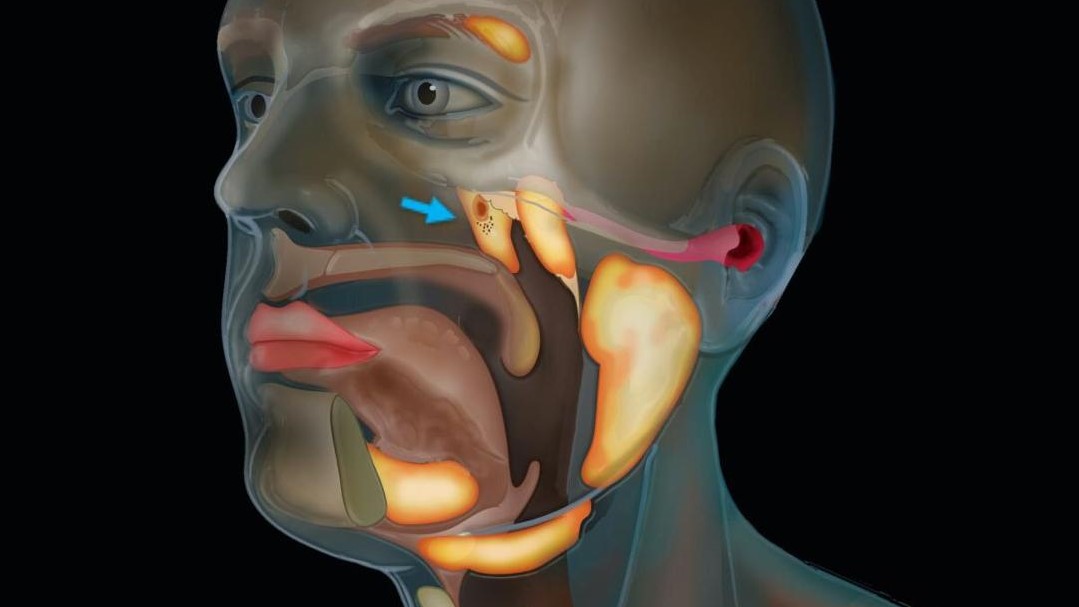

طول مجموعههای تازه کشف شده به طور متوسط حدود 1.5 اینچ (3.9 سانتی متر) است. کاشفان این غدد جدید به دلیل قرار گرفتن در بالای یک غضروف به نام torus tubarius ، آنها را غدد بزاقی توباری لقب دادهاند. این غدد احتمالاً قسمت فوقانی حلق پشت بینی و دهان را مرطوب میکنند. طبق مقالهای که محققان در 23 سپتامبر در مجله Radiotherapy منتشر کردهاند،

این کشف به طور تصادفی شکل گرفت و محققان سرطان در هلند از ترکیبی از سی تی اسکن و توموگرافی انتشار پوزیترون (PET) به نام PSMA PET-CT برای مطالعه سرطان پروستات استفاده کردند. در اسکن PSMA PET-CT ، پزشکان یک “ردیاب” رادیواکتیو به بیمار تزریق می کنند. این ردیاب به خوبی به پروتئین PSMA متصل می شود که در سلولهای سرطانی پروستات افزایش یافته است. آزمایشات بالینی نشان داده است که اسکن PSMA PET-CT در تشخیص سرطان پروستات متاستاز شده بهتر از تصویربرداری معمولی است.